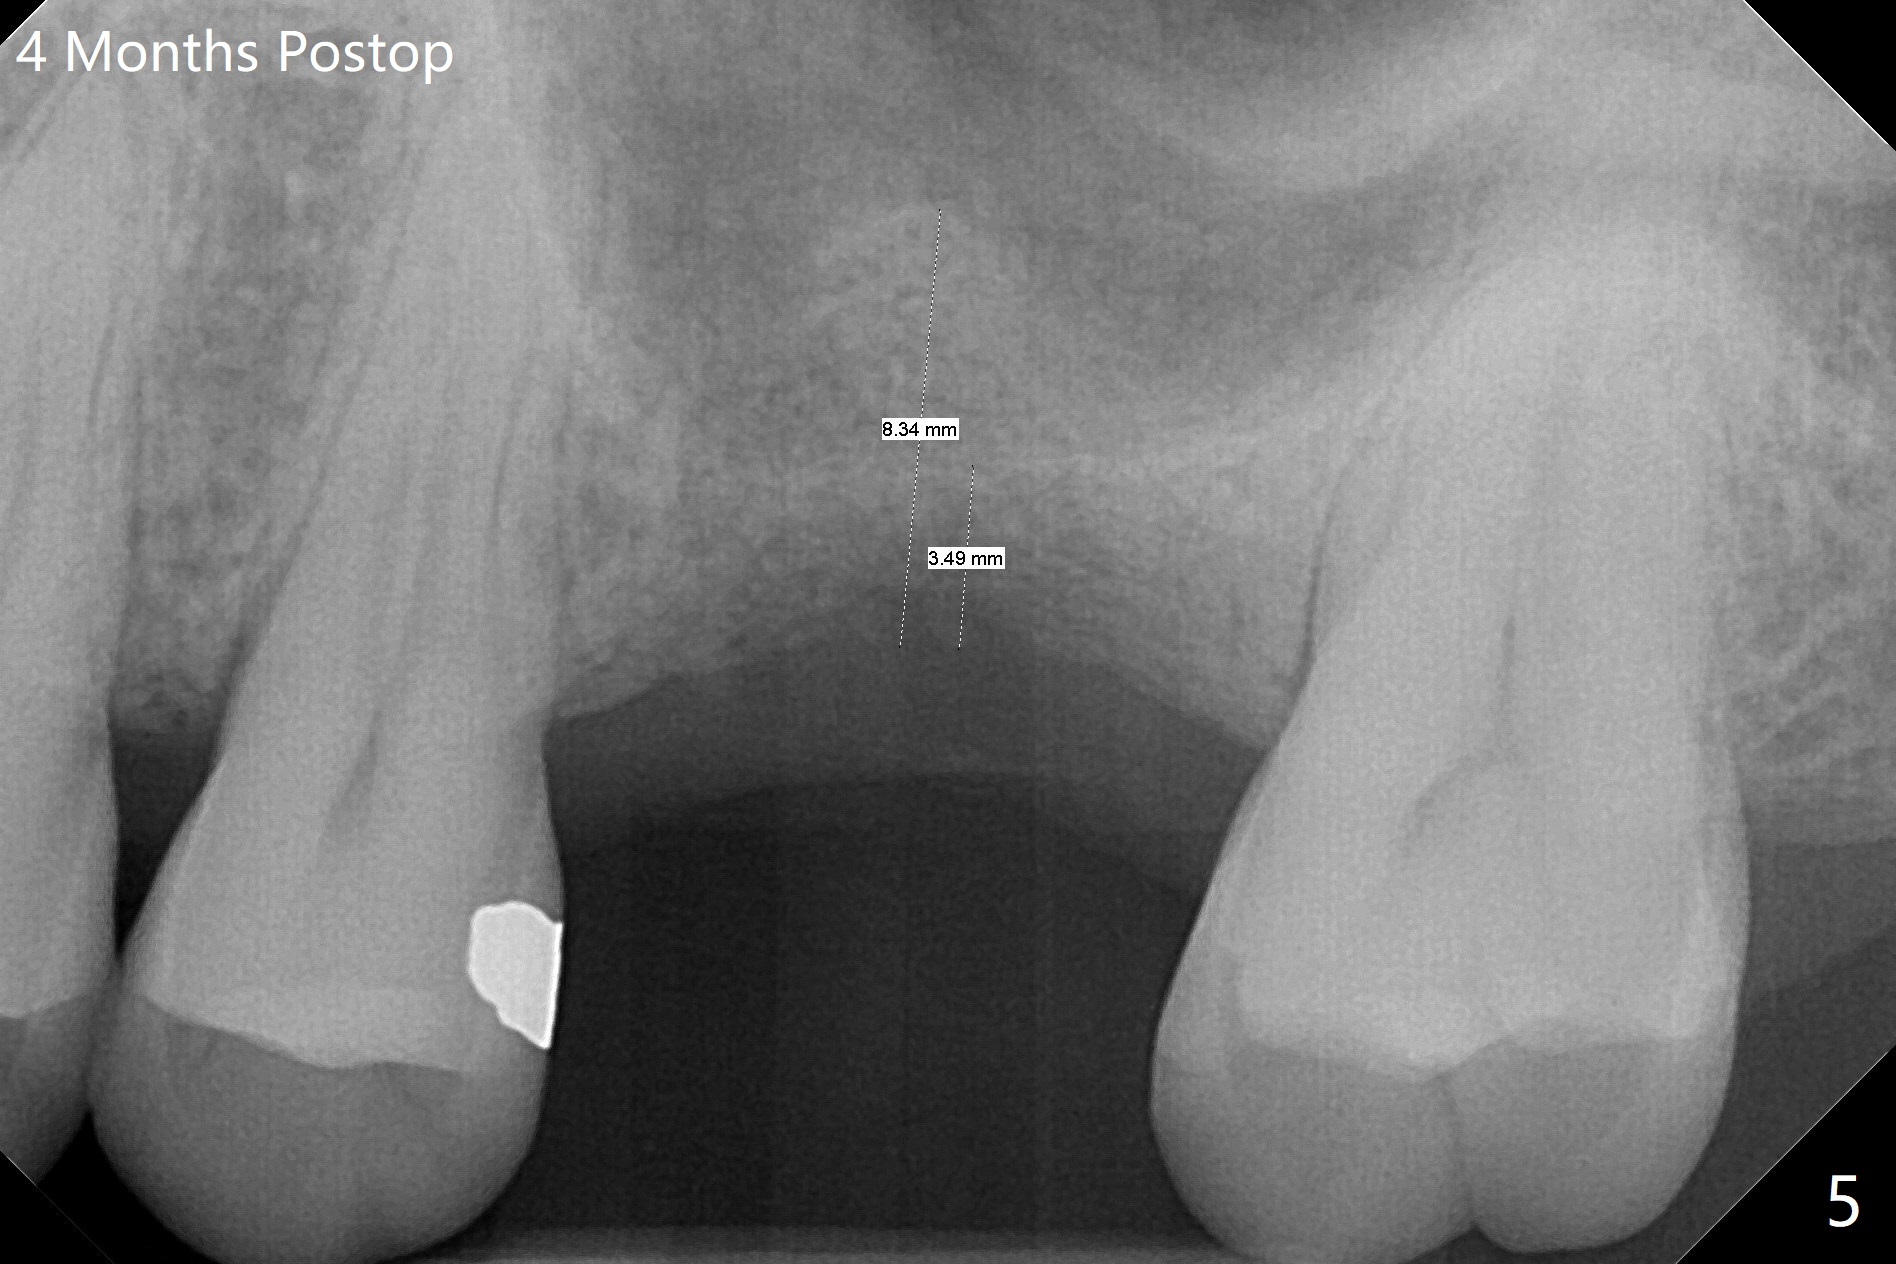

When the crown and abutment at #14 are removed, the implant is found to be shallowly placed. Upon incision, the implant threads are exposed circumferentially and coronal to the buccal crest (Fig.1 *). It seems to be difficult to expect bone regeneration post bone graft. The implant (6.4x6 mm) is removed with a 7/8 mm trephine bur, followed by sticky allograft (Fig.2 *), PRF membrane and 6-month membrane. In spite of the setback, the bone height increases from 3.9 mm to 11 mm due to sinus lift associated with the previous implant placement (Fig.2 L). The depth of the 2nd placement will be controlled by surgical guide. When the periodontal dressing dislodges 11 days postop, the 6-month membrane is lost as well as part of the bone graft. If there is remaining apical native bone, an immediate implant should be placed so that bone graft can be kept in place more securely with an immediate abutment and provisional! The seemingly conservative approach is actually not safe. The wound heals 1 month postop (following dislodgement of the 2nd periodontal dressing, Fig.3). Three months later, consider using bone expanders to do sinus lift and place a SM implant subcrestal. Take PA after 1st expander to the depth. The wound heals 4 months postop (Fig.4), but the bone height (Fig.5) and width (Fig.6) decreases. The latter continues to decrease 9 months postop (Fig.7,8), but bone density is high, average 1360 units. Preparation includes guide, incision, sinus lift, implant placement (possibly tissue-level (9) or FC if the sinus membrane perforates), bone graft, and suture.